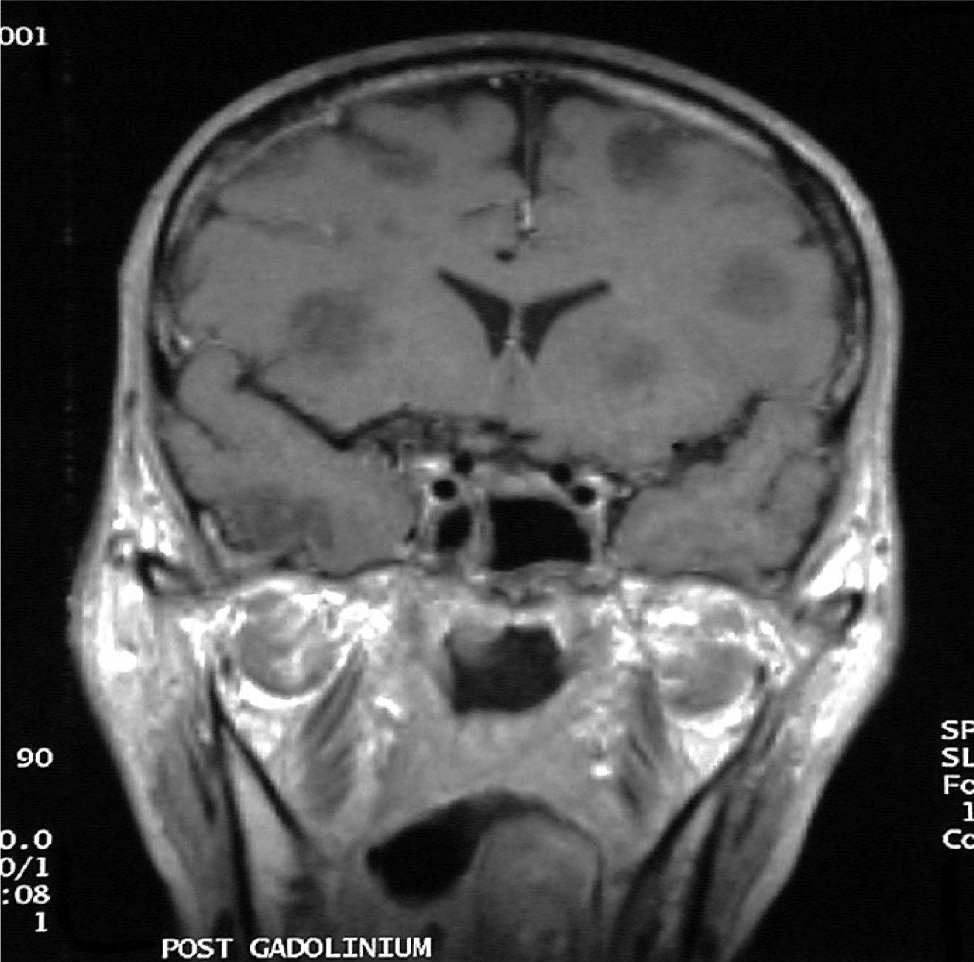

Multiple fungal abscesses in AML – Brain MRI scan